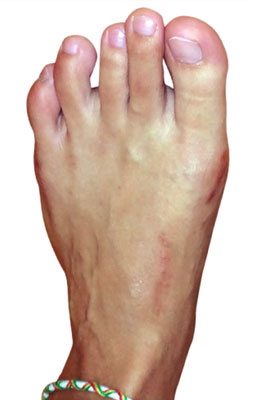

Before

Minimally Invasive Bunion Surgery featuring the CrossRoads miniBunion™ System before

After

Minimally Invasive Bunion Surgery featuring the CrossRoads miniBunion™ System after

Minimally Invasive Bunion Surgery featuring the CrossRoads miniBunion™ System

Eva is a 24-year-old female who had just began working at a job that required high fashion shoes. She was in constant pain but could not take time off work. Our miniBunion™ Minimally Invasive Bunionectomy allowed her to continue to work and be on her foot with full recovery and return to regular shoes by 6 weeks. She had an amazing range of motion, no more bunion pain, and absolutely no visible incision. After picture taken six weeks post-surgery.